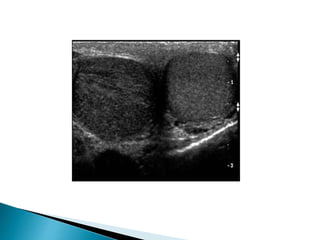

 On ultrasound varicoceles are seen as a

echo-free serpiginous structures measuring

more than 2 mm maximum diameter .

 Visible flow may he seen within larger

varicoceles.

 Their prominence is increased in the

upright position and with the Valsalva

manoeuvre.